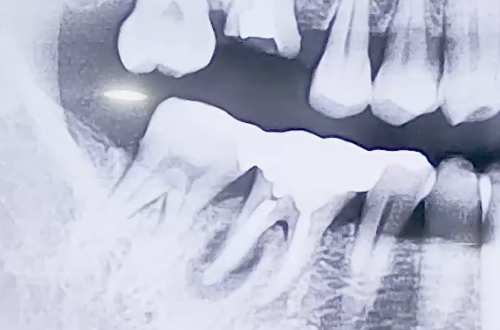

오른쪽 아래 큰 어금니가 굉장히 심하게 붓고 통증이 있는 상태로

내원해 주신 환자분의 사례로, 해당 치아의 흔들림이 심했습니다.

엑스레이를 찍어보니 어금니의 뿌리 중 하나의 주변으로 염증이 생기면서

치아를 단단히 잡아주는 힘이 약해져 흔들리고 통증이 있던 것이었는데요.

때문에 발치 후 임플란트를 시행하기로 하였으나, 발치한 자리 가운데에

식립하기에는 염증으로 약해진 잇몸이 고민스러웠습니다.

때문에 염증을 피해 살짝 옆쪽으로 심고, 염증 부분은 치료한 뒤

뼈이식으로 정리해 드리는 방향으로 치료해 드렸습니다.